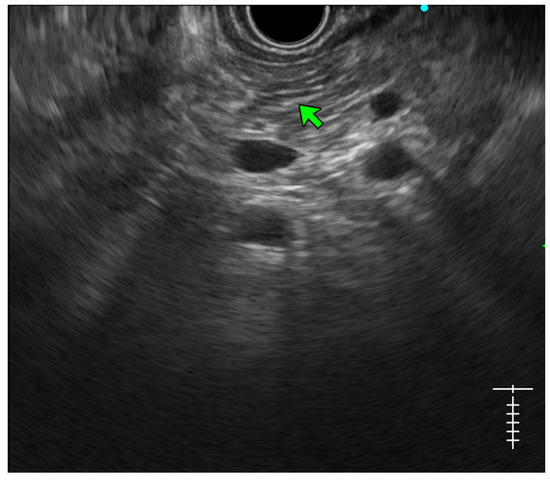

- Lobularity with and without honeycombing: Lobules are described as well-circumscribed reticulated areas ≥5 mm in size, with a relatively hyperechoic rim compared to the adjacent central area. When these lobules are non-contiguous, the EUS pattern is described as ‘lobularity without honeycombing’. When at least three of such lobules are contiguously located in the body or tail region, the pattern is defined as ‘lobularity with honeycombing’ in EUS [30,31]. (Figure 2) The exact histopathological correlation of lobularity is not precisely known. Studies, however, have demonstrated lobularity to correlate with increased fat and collagen in biopsy specimens, and in a recent study, lobularity was demonstrated to be associated with increased disease severity, a higher level of inflammation, and a trend towards a higher grade of fibrosis and atrophy compared to the absence of lobularity in EUS [32,33];